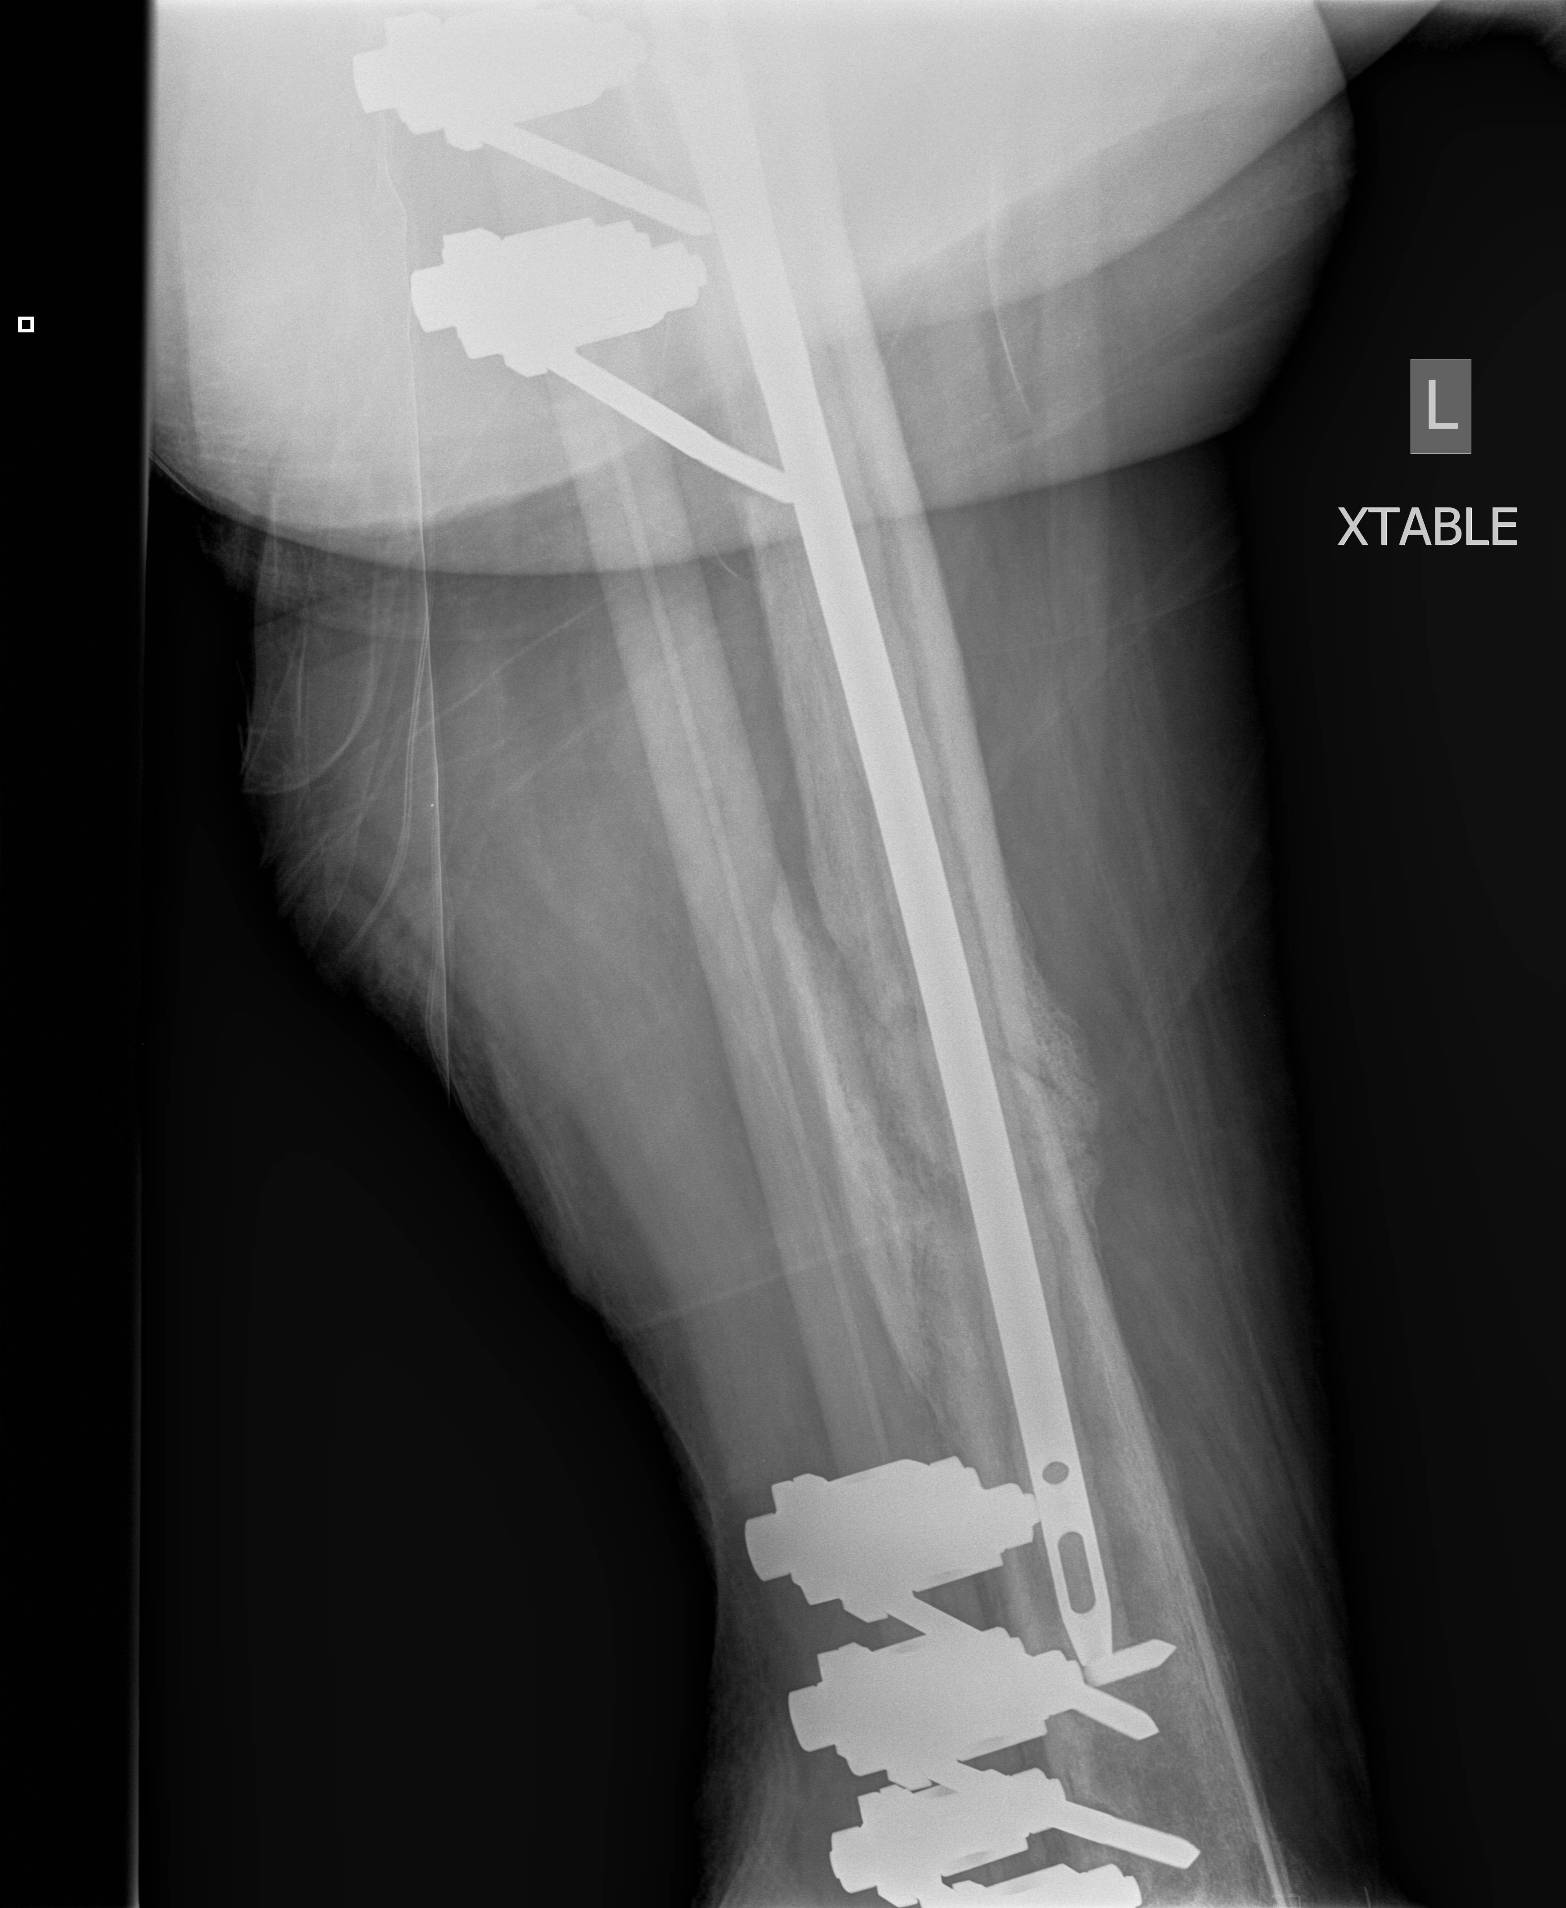

1. Floating Knee

Single incision at knee

- retrograde femoral nail

- tibial IMN if appropriate

High complication rates including non union / malunion, knee stiffness and hetertopic ossification

2. NOF (Neck of Femur) + Femoral shaft fracture

Must pay attention first to meticulous NOF ORIF

Options

1. Pin and Plate NOF / Retrograde Nail

2. Pin and Plate NOF / Plate femur

3. Reconstruction Nail